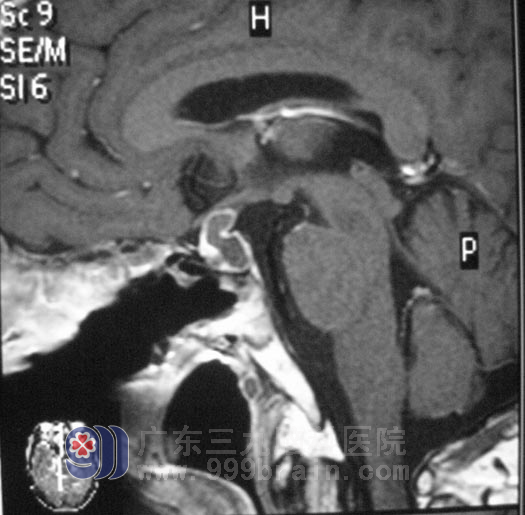

术后磁共振片